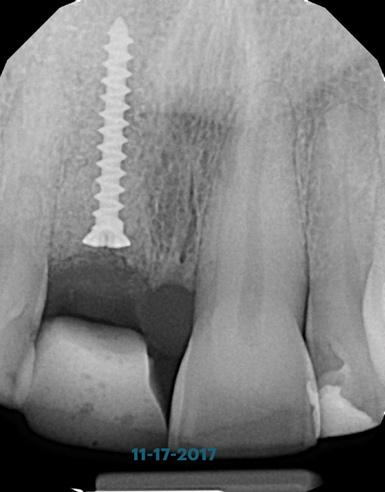

(12.) Radiograph of site No. 8 taken immediately after extraction, guided bone regeneration, and soft-tissue augmentation. Note the tenting screw placed to facilitate vertical bone gain and the bonded temporary Maryland bridge.

Figure 12

A 56-year-old female patient was referred for the evaluation of tooth No. 8 (Figure 4 and Figure 5). A periapical radiograph indicated that the tooth had undergone apicoectomy and received an excessively long post (Figure 6), and a cone-beam computed tomography (CBCT) scan of the site revealed a lack of buccal plate bone (Figure 7).

Based on the single extraction socket roadmap developed by El Chaar and colleagues, the socket of tooth No. 8 was diagnosed as Grade III and would require initial treatment that included the extraction of failing tooth No. 8 followed by simultaneous guided bone regeneration and soft-tissue augmentation by means of a rotated palatal pedicle flap (Figure 8 through Figure 11).27,28 The principles of and guidelines for both the ridge augmentation and rotated pedicle flap have been described in the literature and will not be focused on in this case report.27-30 The patient was temporized with a bonded Maryland bridge that was adjusted to avoid creating pressure on the tissue during healing (Figure 12).